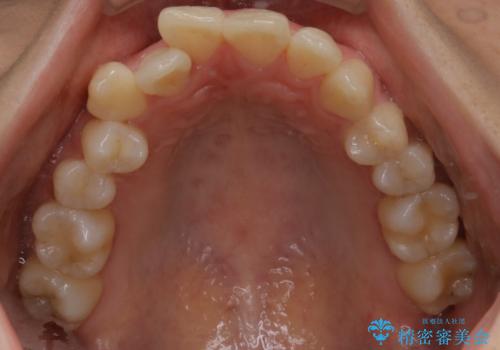

- 前歯のガタつきと噛み合わせの改善を主訴に初診来院され、審査の結果マウスピース装置による非抜歯での矯正を行うこととなりました。

元々の顎骨や口腔・歯槽骨が小さく、どうしても歯が並びきらない状況になっていました。マイクロインプラントという固定源からゴムかけを行うなど、補助装置を活用しながら臼歯部を順番に遠心方向(奥)に移動させていくことで抜歯をしなくても歯が並ぶよう計画を立てました。

歯を並べるスペースを作るために、歯の遠心移動と歯列の拡大、歯自体を少しだけ小さく削る(IPR)という方法を複合的に組み合わせて配列を行いました。遠心移動用のゴムかけにはマイクロインプラントという小さいネジを用いて骨に直接固定源を求めました。